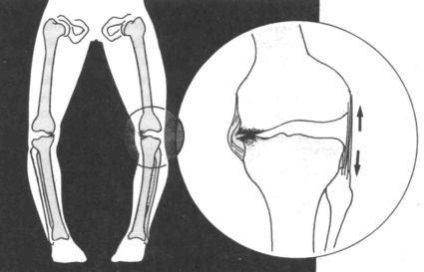

Varus csökkentése láb; a betegség oka és kezelési eljárás

Varus láb öntött részének tekintik a patológiai a mozgásszervi rendszer, amelyben hangsúlyosan ívelt boltívek és stop tengelyeket. crus így vannak olyan távolságra egymástól. A patológiai tűnik, hogy növeli a terhelést a külső oldalán a láb, míg a belső oldalán befelé néző, ami az O-alakú görbülete, növeli a terhelést az alsó végtagok, a gerinc. Ennek következtében alakváltozás a lábát a gyerekek sok komplikáció merülhet fel a jövőben, amelyek közül megtalálható a progresszió lúdtalp, varus combnyaktörés idején az őszi, gyakori ficamok és subluxations lábszár, a térd ízületi, osteoarthritis, gonartrózis.

Külsőleg varus láb staging emlékeztető dongaláb a gyerekek, de a betegség ezzel szemben fordítva. Dongaláb minősül rendellenes görbület a boka. térd ízületi és a lábak, amely megnyilvánul az első nappal a születés után, vagy úgy tekintendő, hogy egy születési rendellenesség. A dongaláb okoz örökletes patológia, komplikációk a terhesség alatt, ugyanakkor a lábát varus tekinteni szerzett formája görbület. Varus görbület után jelenik meg 3 - hónapos korban leggyakrabban idején növeli a terhelést a láb, azaz egy év után az élet, és egyre inkább okoz patológia kapcsolatos tényezők a gyermek tevékenységgel, annak érését.

A fő tünet varus görbület - ez görbe lábak. Csavarás O-alakú, aminek következtében a gyermek limps séta közben, beszél, mintha imbolygott az egyik oldalról a másikra. A természet a tünetek mértékétől függ a görbület. Így az első fokú megjelennek kisebb fájdalom, nehéz megtalálni a kényelmes cipő. By the way, a lassú progresszió tűnhet enyhe görbületét, amiért a betegség serdülőkorban észrevétlen maradhat. Ezért amellett, hogy a görbület a lába, meg kell helyezni a hangsúlyt, mint jelek:

Csökkentett értékcsökkenés stop funkció növeli a terhelést más ízületek, a gerinc, ezért gyakran van fájdalom bennük. Mivel a deformáció az ívek és a csökkent mozgásképességű ízületek boka, térd, elsorvad része az izmok és szalagok. Mint egy gyerek, vagy egy felnőtt szenved gyakori rándulások, ficamok, törések, és ha egy törött nyak combcsont, a hosszú távú rögzítését egy végtag nem tenné gyógymód varus deformitás műtét nélkül. csípőtörés amikor varus deformitás gyakran vezet a lerövidítése a végtag, amely veszélyezteti a beteg a fogyatékosság és kialakult osteoarthritis, térdízületi gyulladásban.